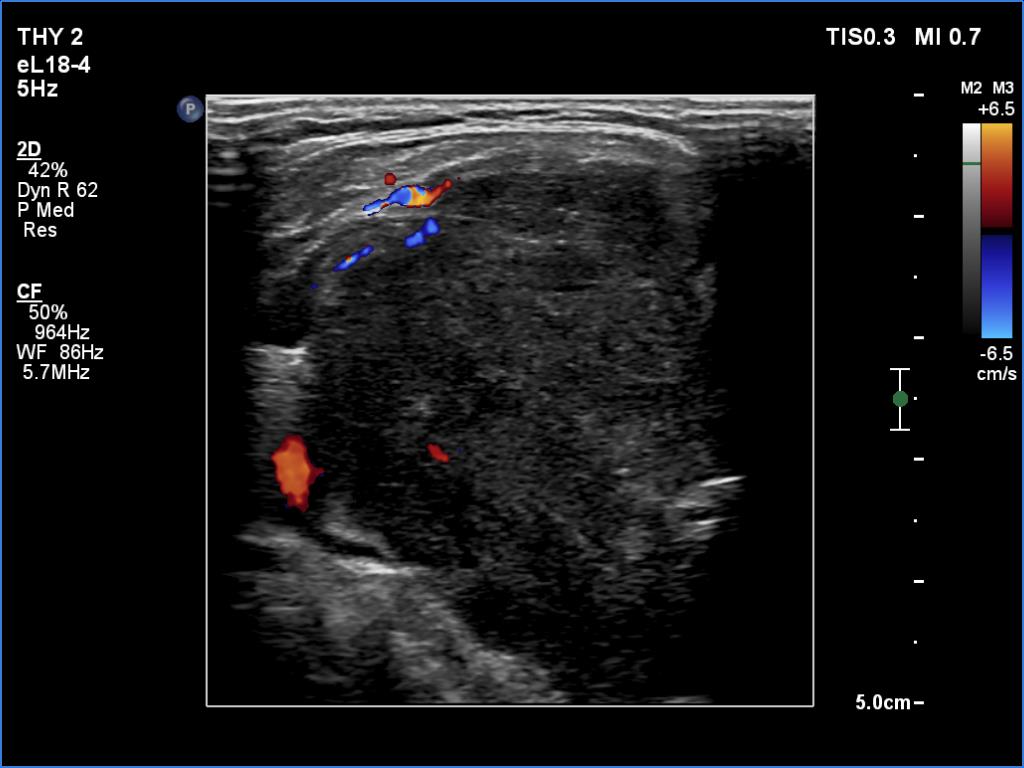

Thyroid cancers - case 1174 (ultrasonographic picture 8)

Right lobe, transverse view, color Doppler mode. The nodule is almost avascular.